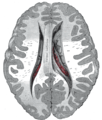

Transverse Cut of Brain (Horizontal Section), basal ganglia is blue | |

The caudate nuclei are located near the center of the brain, sitting astride the thalamus. There is a caudate nucleus within each hemisphere of the brain. Individually, they resemble a C-shape structure with a wider "head" (caput in Latin) at the front, tapering to a "body" (corpus) and a "tail" (cauda). Sometimes a part of the caudate nucleus is referred to as the "knee" (genu).[5]